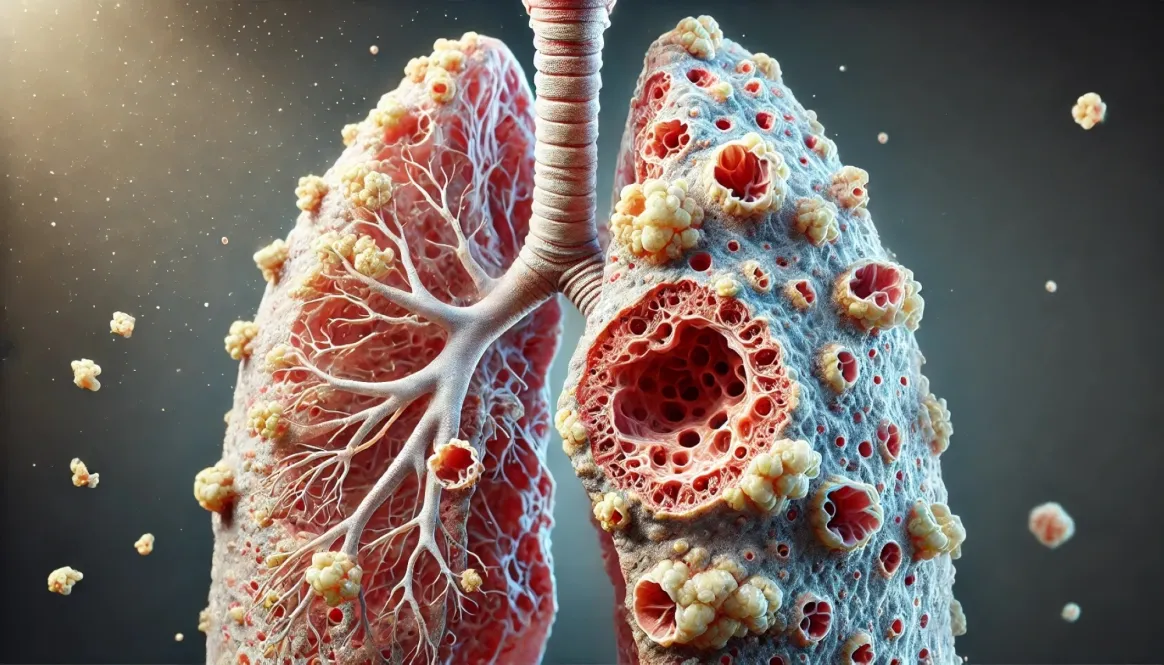

كشفت دراسة حديثة أُجريت بجامعة “هوا تشونغ” الصينية، حالة خلوية جديدة داخل أورام سرطان الرئة تُعرف بـ”الخلايا عالية المرونة”، والتي تُعَدّ عاملًا رئيسيًا في مقاومة العلاج وتقدّم المرض، حيث تمنح رغم قلّتها الورم مرونة كبيرة في التكيّف مع الضغوط العلاجية.

وأظهرت النتائج المنشورة بمجلة “Nature” العلمية، أن هذه الخلايا تعمل كمحرّك لتنوّع الخلايا السرطانية داخل الورم، إذ تولّد خلايا سريعة النمو وأخرى قادرة على النجاة من العلاجات، وذلك اعتماداً على تقنيات تتبّع الخلايا الخلوية التي تسهم في الانتقال من المراحل المبكرة إلى المتقدمة من المرض.

كما تبيّن عند اختبار الاستجابة للعلاج، أن الخلايا المشتقة من هذه الحالة عالية المرونة تقاوم العلاج الكيميائي والعلاجات الموجّهة، في حين تتراجع الخلايا الأخرى، كما أظهرت التجارب أن استهداف هذه الخلايا أو تقليل وجودها يؤدي إلى انخفاض نمو الورم وتأخير ظهور المقاومة العلاجية. وفق “أخبار 24”.

وتشير الدراسة إلى أن مقاومة علاج سرطان الرئة لا تعود فقط إلى طفرات جينية ثابتة، بل إلى مرونة خلوية ديناميكية تسمح للورم بالتكيّف السريع، ما يفتح الباب أمام استراتيجيات علاجية جديدة تركّز على تعطيل هذه الحالة الخلوية، لتعزيز فعالية العلاجات الحالية.